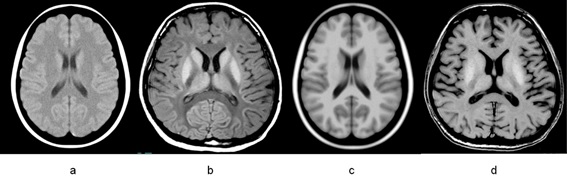

Linear regression result between tissue relaxation time and body temperature was T1=900+32.6T for gray matter and T1=691+3.5T for white matter, respectively. As shown in Figure 1, simulated PM-MR Images at arbitrary temperature could be generated using the proposed system. Arbitrary slice location could be simulated using interactive slice prescription interface. User could simulate both unfixed and fixed PM-MRI scan protocol. As shown in Figure 2, Contrast reverse effect of gray matter and white matter associated with body temperature was able to reproduced with simulation. FLAIR inversion time change with temperature could also be simulated as shown in Figure 3. Fixed and Unfixed brain MR contrast simulation result for T1 weighted imaging is shown in Figure 4.

Figure 2 Simulated PM-T1 weighted image. a: simulated spin echo (SE) image with TR 550ms, TE 12.5ms, body temperature 4 degree. b: acquired SE image with the same scan parameter [3]. c: simulated spoiled gradient echo (SPGR) image with TR 25ms, TE 5ms, FA 30 degree, body temperature 4 degree. d: acquired SPGR image with the same scan parameter [3].